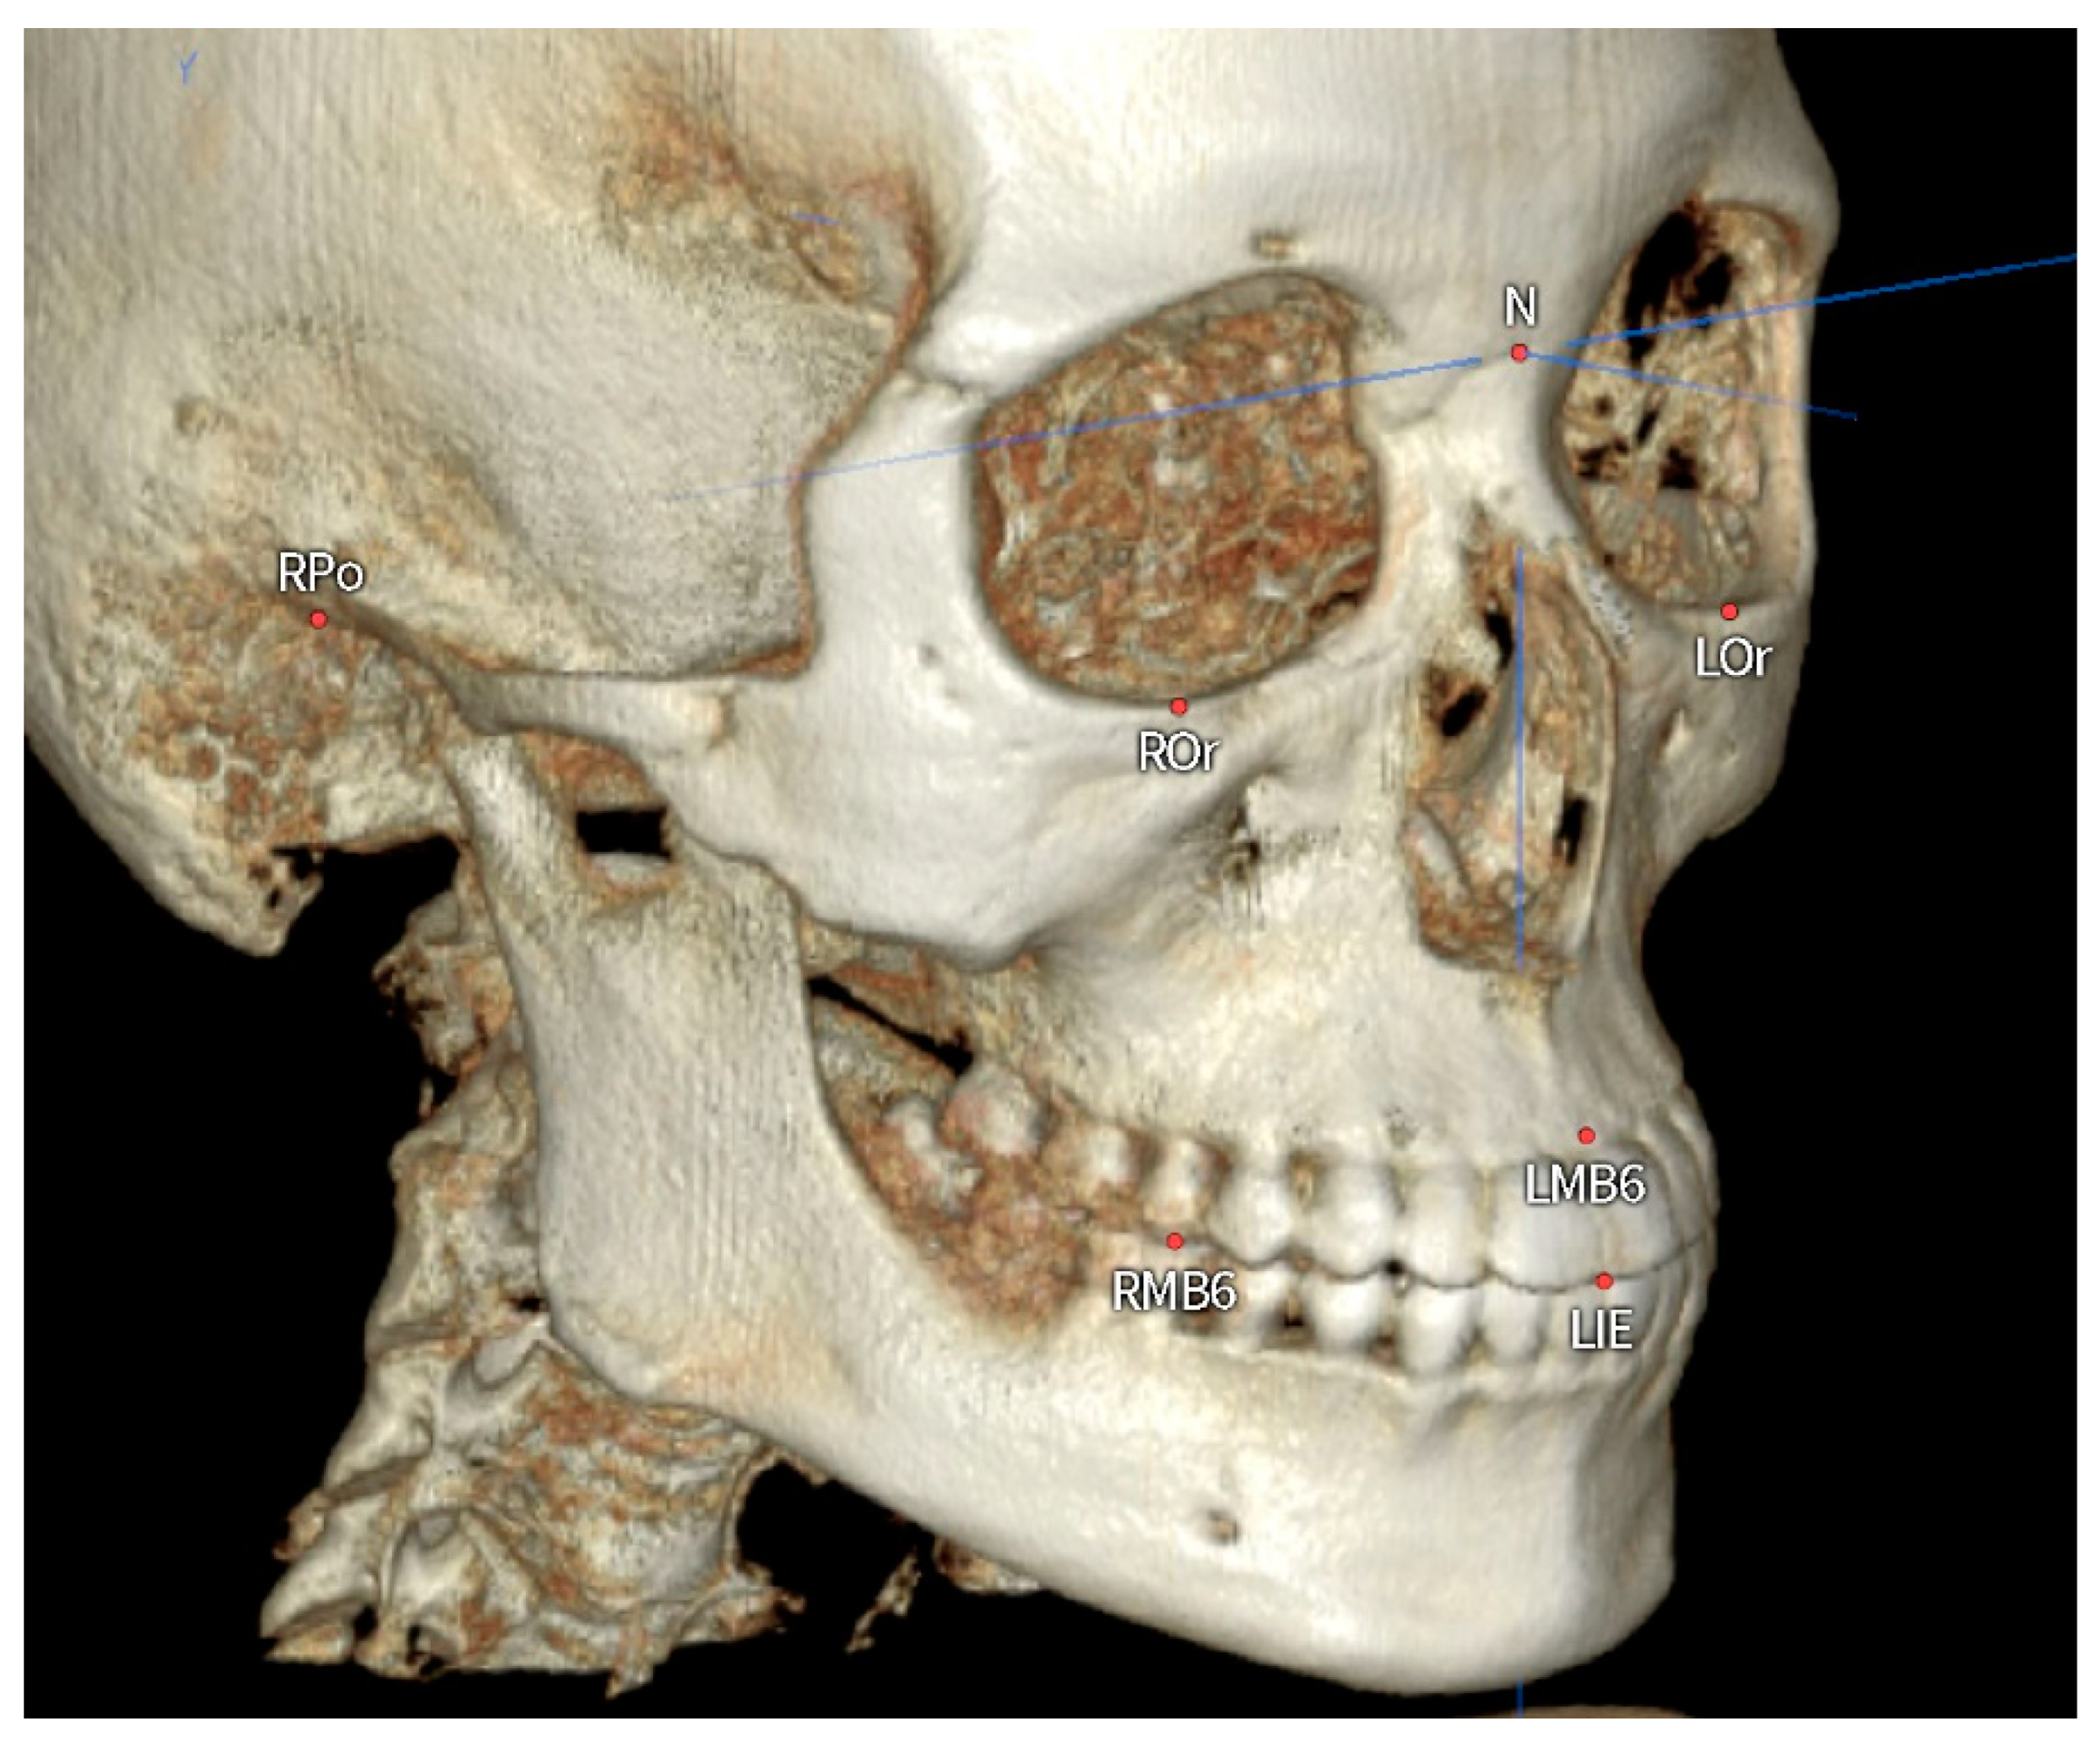

Original CBCT data of the 145 patients (84 men, 61 women, mean age: 22.0 ± 1.76 years) were stored in digital imaging and communications in medicine format and analyzed using Ondemand3D software (Version 1.0, Cybermed, Seoul, Republic of Korea). Two-dimensional lateral and frontal cephalograms were obtained from the reoriented CBCT images (Figure 1).

Figure 1.

Reference planes and landmarks for reorientation of the CBCT images. Nasion, right and left orbitale and right porion were used for reorientation to generate two-dimensional cephalographs. The mandibular occlusal plane was formed by the lower incisor edge (LIE) and right and left mesiobuccal cusps of the mandibular first molars (RMB6, LMB6).

CBCT images were reoriented such that the mandibular occlusal plane passed through the midpoint of the mandibular central incisor edge and right and left mesiobuccal cusps of the mandibular first molar (Figure 1) [2]. The distances between the left and right mandibular molar roots and the inner and outer surfaces of lingual cortical bone were measured (Figure 3).